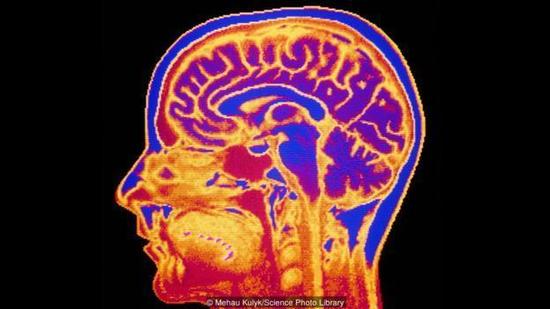

图:我们的脑子里到底发生了什么?